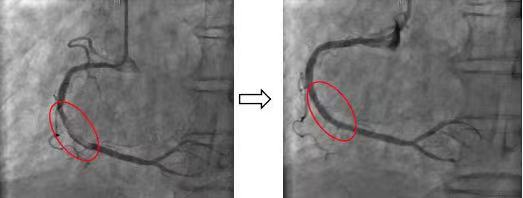

急诊冠状动脉介入术中,手术团队迅速锁定患者右冠脉内大量血栓,为患者进行了冠状动脉内血栓抽吸术、冠状动脉内球囊扩张术,并顺利植入一枚最新一代药物洗脱支架。术后患者的胸痛症状立即缓解,收入心脏内科重症监护室进行后续治疗。

患者影像